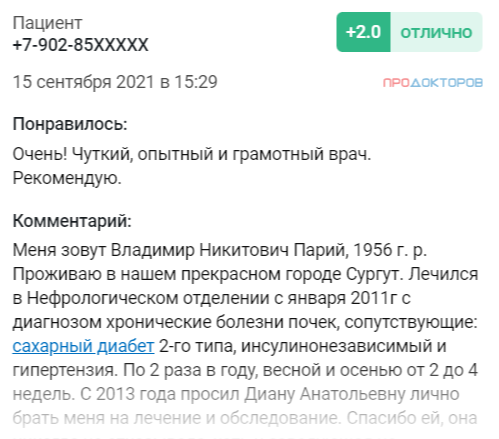

Отзывы

Все отзывы обо мне вы можете почитать на популярном портале Продокторов или оставить свой отзыв о моей работе.

Рейтинг на Продокторов